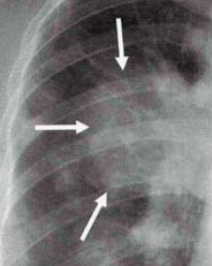

엑스레이로 폐렴을 진단하는 방법을 찾아봤다. 폐 부분은 원래 검은색이어야 정상이라고 한다. 염증이 심각할수록 하얀 부분이 많다고 한다. CT로 보면 엄청 잘 나오는데, 비싸서 X-ray를 많이 쓴다고 함.

이런 느낌으로 되어 있으면 폐렴인 것 같다.